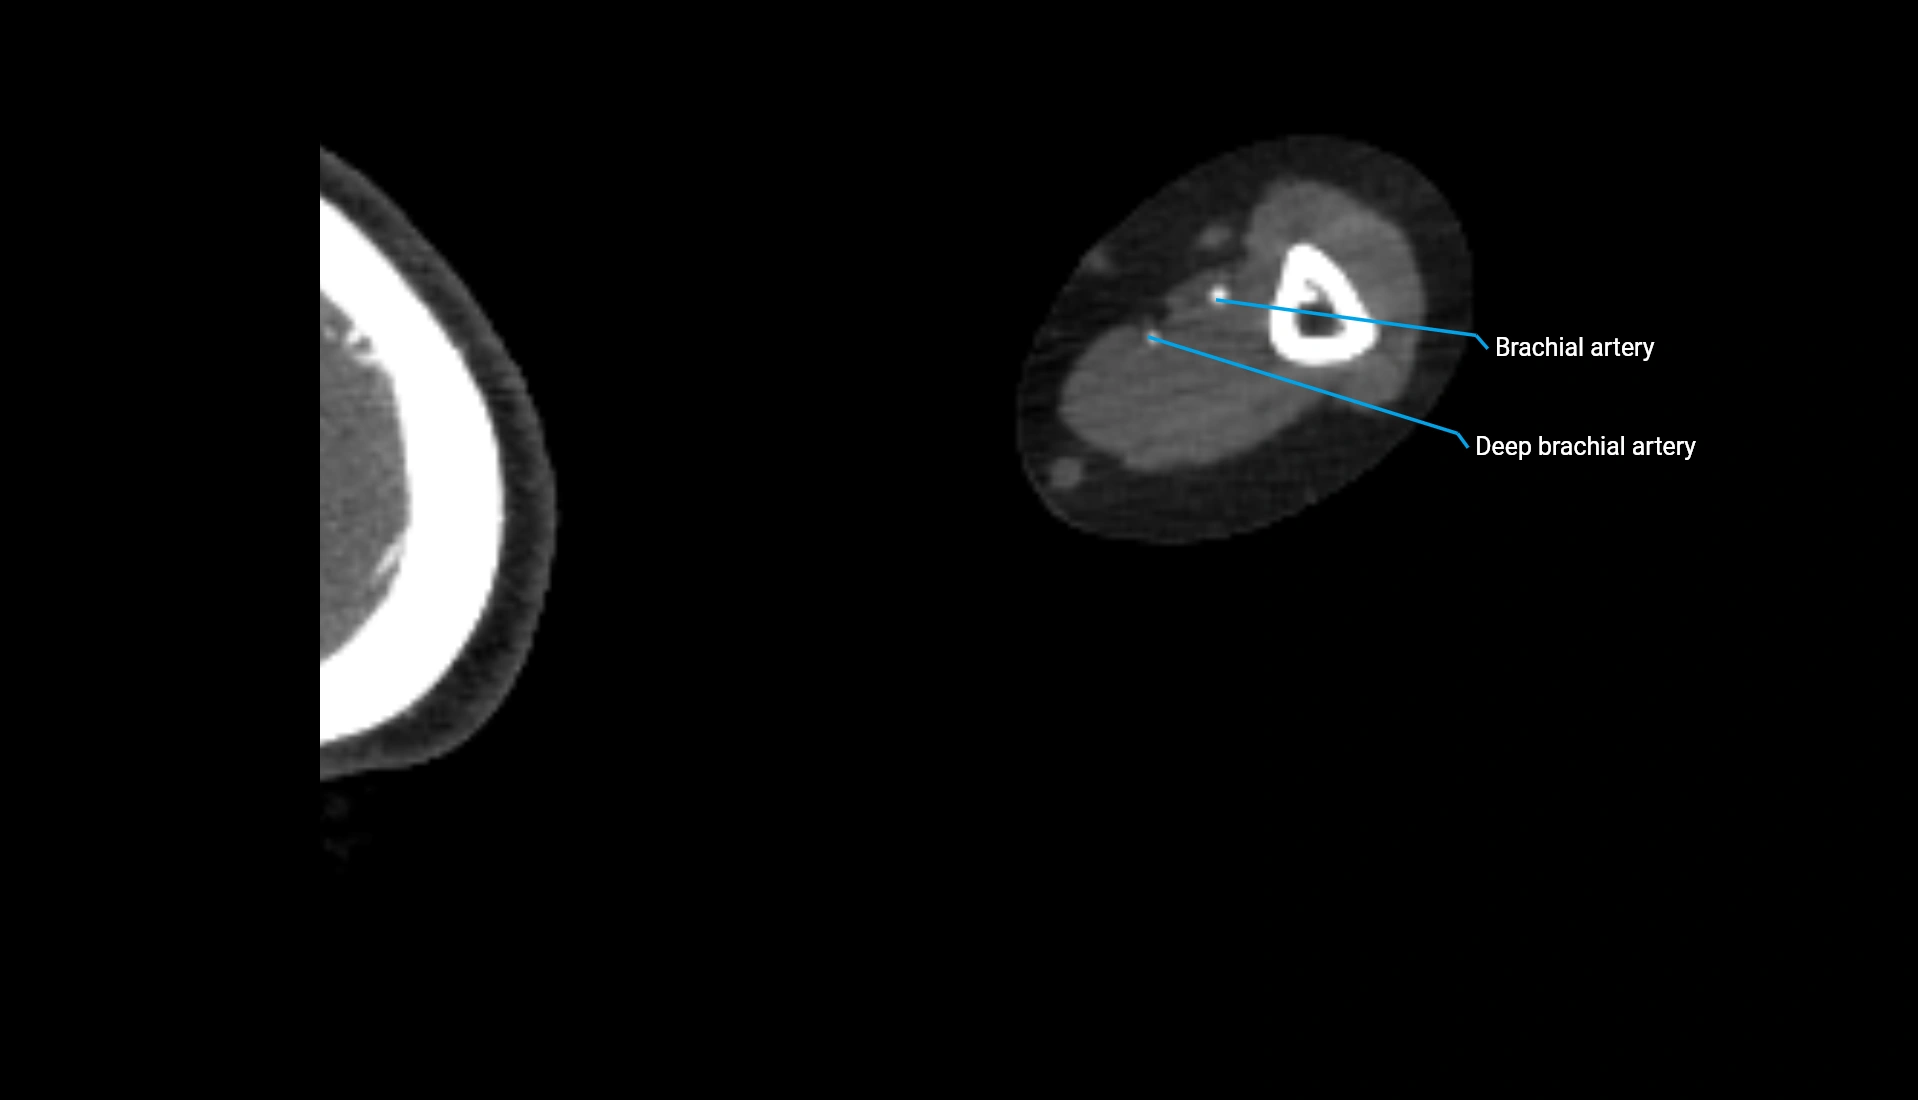

CT Appearance

Non-Contrast CT:

• Cortex: High-density, sharply defined

• Subchondral bone: Dense cancellous matrix

• Articular surface: Smooth concave contour articulating with the capitellum

• Excellent for evaluating bone integrity, alignment, and subtle fractures

Post-Contrast CT:

• Bone: No enhancement

• Joint capsule and synovium: Mild enhancement outlining the joint

• Improves contrast between soft tissues and bony margins

• Useful in detecting subtle joint abnormalities or postoperative changes